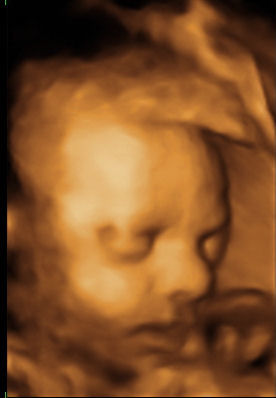

Huh, jó sokat írtatok, mióta nem voltam. Kösszi a bíztatást, én is reménykedem, hogy magától elmúlnak azok a tágulatok. Nagyanyám mondta, hogy Bencének ( ő az unokaöcsém, 18 hónapos ) valami ciszta volt a fejében, a fejtető alatt, de mire megszületett, magától felszívódott. Szóval ha az eltűnt, ennek is el kell tűnnie.